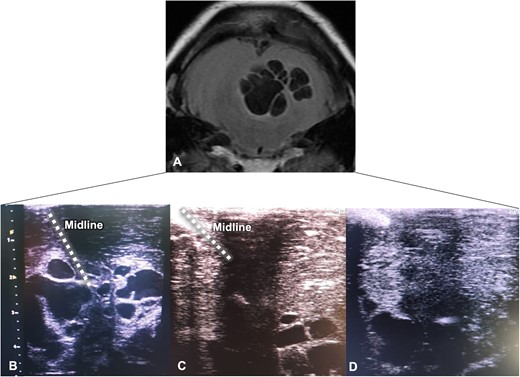

The patient was placed in a Concorde position, and a standard sub-occipital craniotomy was performed. Drilling of the occipital rim and a double Y-shaped durotomy ensured greater visualization of the supra-cerebellar infratentorial corridor. Subsequently, the resection of parasitic lesions was assisted by utilizing a 2D ultrasound linear transducer (Samsung® Medison Sonoace X6). By correlating the cyst depth locations in the MRI, the transducer provided visualization of lesions from the most profound plane (located at 4 cm) up to the surface (Fig. 3A and B). Mobilization of the transducer in acute angles from the midline increased the angle of attack for the complete resection of lesions (Fig. 3B–D). Lesions were sent for histopathological examination, confirming the diagnosis of Taenia solium cysts. A postoperative CT without contrast corroborated the complete resection of cysts (Fig. 4A).

Intraoperative ultrasound-guided resection. (A) Cerebellar MRI is shown upside down for better correlation with the ultrasound view; parasitic cysts correspond to hypointense lesions; (B–D) Echographic views depicted the progression of ultra-sound guided resection with excision of the hypoechoic lesions from the superficial to deep planes.